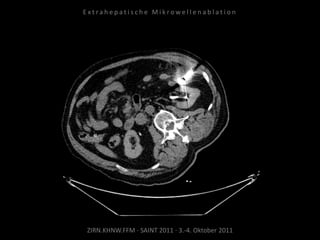

Ablation am 17.08.2010

Metastase lateral der linken Niere:

1 Nadelposition.

Metastase medial des linken

Musculus iliacus: